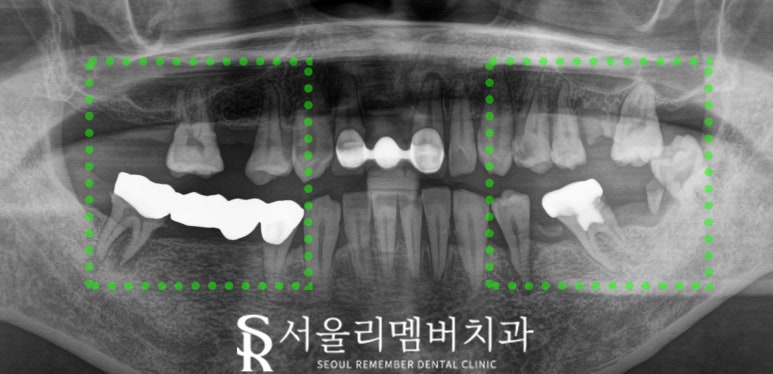

구강 검진을 실시한 결과,

위아래 어금니 대부분에서 치주염과

심한 충치로 파손된 상태입니다..

일부는 흔들리거나 빠져 있고,

치경부 마모도 진행되어 전체 개선이

필요한 상황입니다.

x-ray를 통해 더 자세히 살펴본 결과,

치주염으로 인하여 치은 퇴축이

일어나고 있고 몇몇 치아는

염증까지 있습니다.

이 경우에는 발치를 피할 수 없죠.